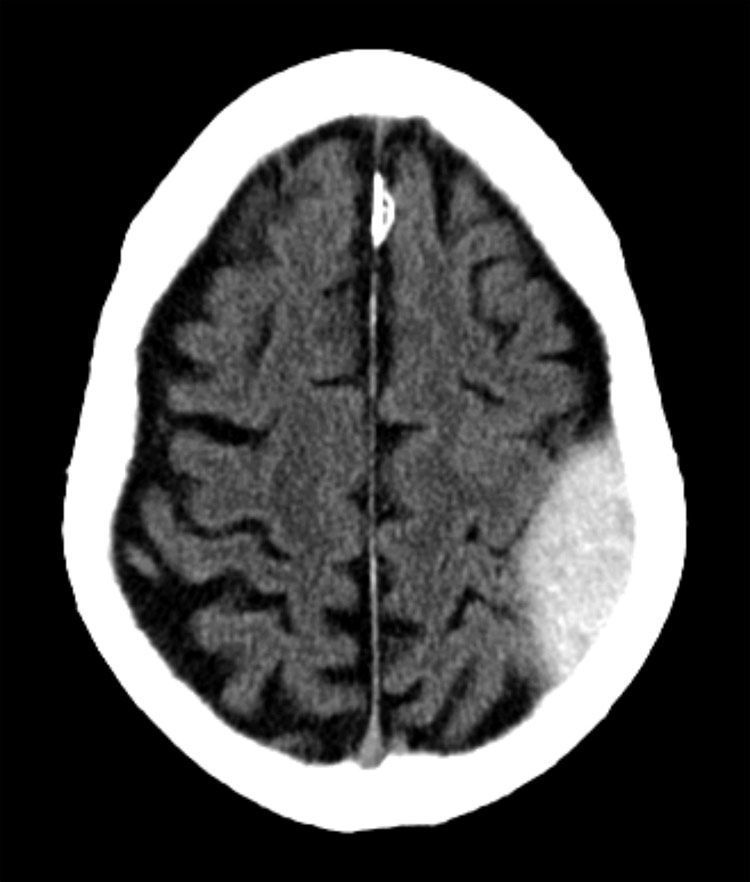

CT BRAIN QUIZ: Alcoholic found unconscious. What does the image show?

A: Subdural haematoma

B: Subarachnoid haemorrhage

C: Intraventricular haemorrhage

D: Extradural haematoma

E: Intracerebral haemorrhage

Start Quiz bit.ly/3F2dhB8